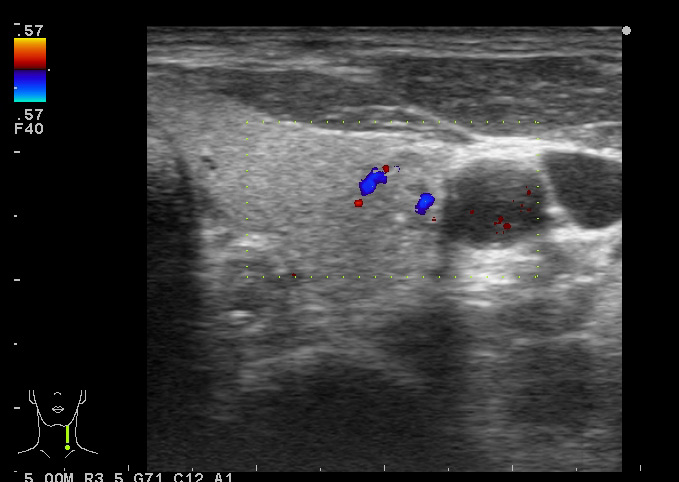

Папиллярная карцинома, УЗИ

Мужчина средних лет.

изоэхогенный узел с кальцинатами

Типичная картина, кстати.

Папилляная карцинома.

Диагноз доказан морфологически (ТАБ, гистология).